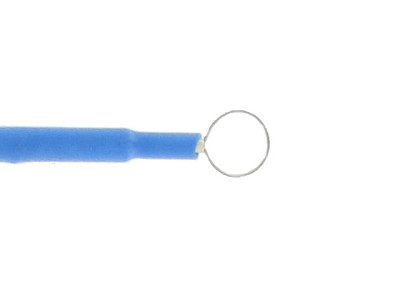

Elettrodo ad ansa - retto diam. 8 mm - 5 cm - conf. 6 pz.

Codice Articolo: CH30333

Codice EAN: 8033638322314

Marca: GIMA